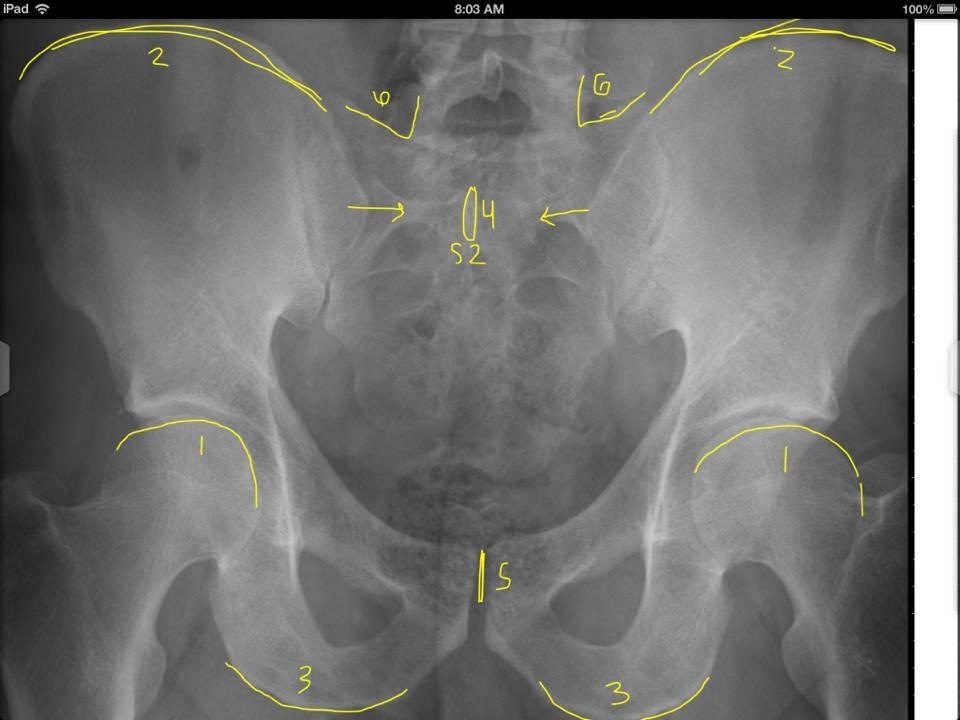

Ocipital Condyles

Foramen Magnum

Lateral Masses of C1

C1 TVP/Lateral Mass Junction

Odontoid Process

C2 Spinous Process

C2 Pedicle shadow